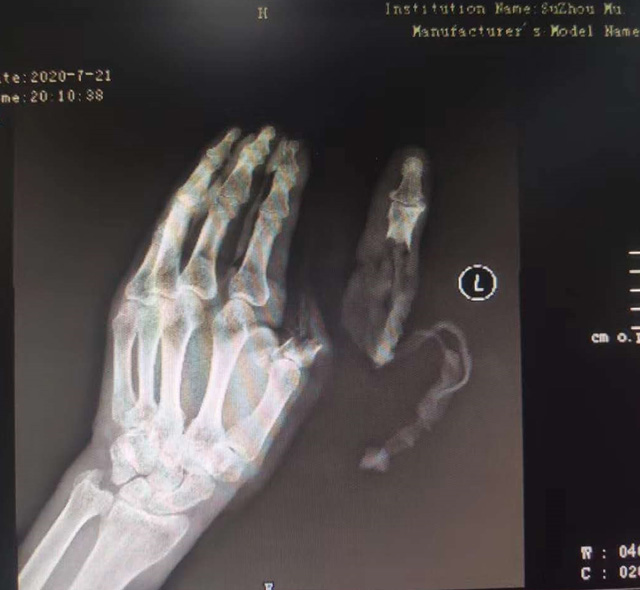

現(xiàn)代快報(bào)記者了解到,7月21日下午,這名76歲的老人在家擦拭面粉機(jī)時(shí),忘記關(guān)閉電源,結(jié)果抹布被纏進(jìn)機(jī)器,順帶著將老人的手也帶進(jìn)機(jī)器中。老人奮力掙脫,可為時(shí)已晚,待將手取出時(shí),已經(jīng)血肉模糊,大拇指在脫落后還被絞入機(jī)器軋了一圈……

△老人送醫(yī)時(shí)的手部狀態(tài) 蘇州市立醫(yī)院供圖

拇指可以影響一只手40%的功能,為此醫(yī)院立即制定了手術(shù)方案,決定為老人進(jìn)行斷指再植術(shù),盡力為其保住拇指。由于該患者年紀(jì)大、血管彈性差,動(dòng)脈血管分層也很嚴(yán)重,面對(duì)重重困難,醫(yī)生在顯微鏡的輔助下,小心翼翼地將血管、神經(jīng)重新吻合,并修復(fù)肌腱、皮膚。經(jīng)過(guò)5個(gè)多小時(shí)努力,最終再植成功。